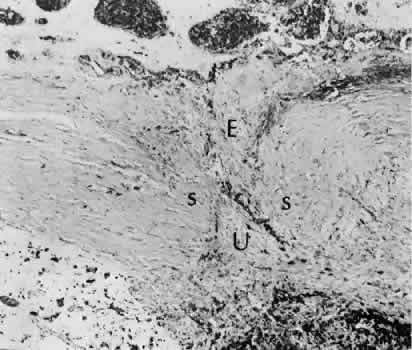

Iris cyst formation (Figs. 45 and 46 is also caused by implantation of surface epithelium onto the iris at the time of surgery or trauma. The cyst generally grows slowly and is accompanied by peripheral anterior synechiae. If extensive, the cysts may cause a secondary chronic closed-angle glaucoma. Histologically, the cyst is lined by stratified squamous or columnar epithelium, sometimes containing mucous cells, and is filled with keratin debris (white or pearly cysts) or mucous fluid (clear cysts).

Fig. 45. Two cases of epithelial iris cyst formation following cataract extraction. A. Instead of forming a flat sheet to cover the posterior cornea and the anterior iris, the invading epithelium has formed a cyst in the anterior chamber. The cyst usually retains some continuity with the original wound but also may become free-floating in the anterior chamber. B. In this case, there is extensive distortion of the iris. The type of ingrowth, sheet or cystic, is a major determinant of the method of treatment used. C. The histologic character of the cyst lining indicates the presence of goblet cells. The origin of these cells may have been from the conjunctiva. In this rare circumstance, the cyst may become filled with mucous. (Hematoxylin-eosin stain; × 101.)

Fig. 46. The contents of an epithelial cyst and the consequences of an epithelial presence. A. The histologic section of this case of epithelial ingrowth demonstrates the presence of both a Soemmering's ring cataract and an epithelial inclusion cyst. Squamous epithelium desquamates surface cells as part of its renewal process. In this case, the cyst is filled with desquamated debris. The desquamated debris, if liberated into the anterior chamber, will evoke an extreme inflammatory reaction similar to that encountered with a ruptured dermoid cyst of orbital soft tissue. (Hematoxylin-eosin stain; × 10.) B. High magnification of the cyst wall shows that the epithelium has become differentiated. The desquamating surface is clearly differentiated from the more primitive-appearing basal cells. Degenerated surface cells will fill the cyst cavity. The underlying stroma of the iris, originally diaphanous in character, has become coarse and compact because of the influence of the invading epithelial cells.